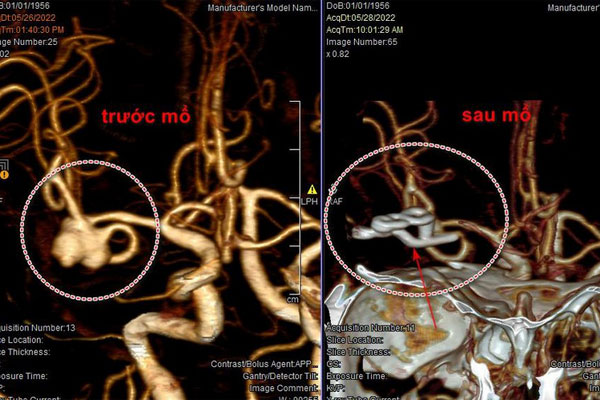

Hình ảnh chụp CT cho thấy bà V. bị vỡ mạch máu não trước và sau điều trị. Ảnh: BVCC

Tại đây, sau khi chụp CT, các BS chẩn đoán bà V. bị xuất huyết khoang dưới nhện do vỡ phình mạch máu.

Các BS nhanh chóng phẫu thuật kẹp cổ túi phình cầm máu, đồng thời lấy máu tụ đã chảy chung quanh túi phình.

Sau 5 ngày mổ, sức khỏe bà V. ổn định, phục hồi tốt, bớt đau đầu, không yếu liệt.